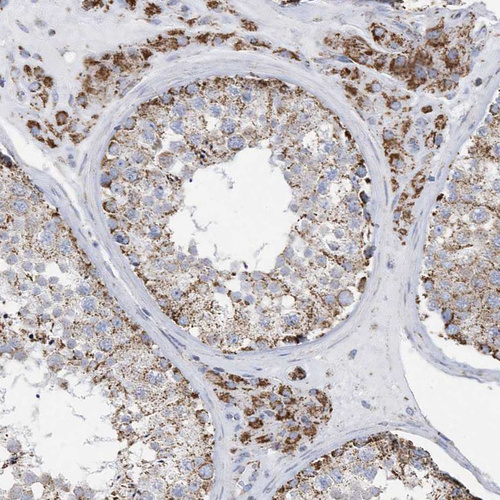

Immunohistochemical staining of human testis shows strong granular cytoplasmic positivity in cells in seminiferous ducts and Leydig cells.